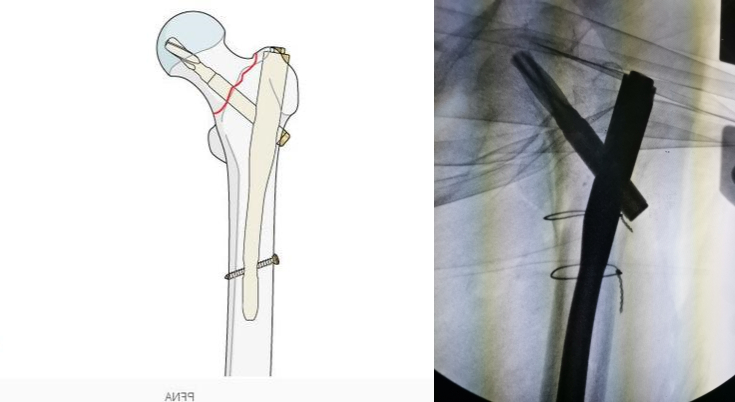

手法复位成功可以大大减少手术时间,避免皮肤切开后老人一边流血一边复位,从而增加出血量。在手法复位后,可以使用可移动的X线机进行透视,查看复位的情况,如下图所示,复位基本满意后就可以开始手术:

复位前后比较

手术首先切开皮肤,严重粉碎的股骨粗隆间骨折可以进行钢丝固定,这一步对于简单的骨折可以省略。该患者骨折粉碎,移位明显,必须进行钢丝的固定,在钢丝固定后我们欣喜地发现骨折已经完全复位:

钢丝固定

在完全复位后就可以进行髓内钉内固定的操作,我们将髓内钉插入骨髓腔,对骨折断端进行固定:

髓内钉